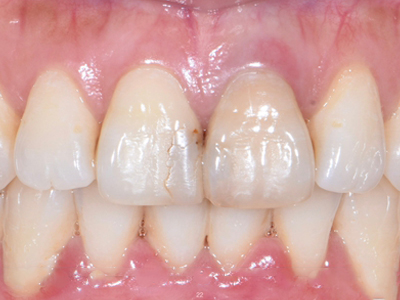

牙龈退缩上排牙齿的牙根轻微露出图

牙龈退缩患者的上排切牙、尖牙处的牙龈发生回缩,从而造成牙根轻微暴露。是由于牙周炎治疗、不良刷牙习惯等因素引起,牙齿敏感需要脱敏治疗。